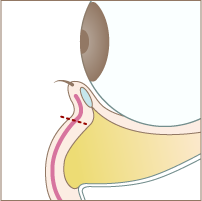

Treatment Step施術手順

Step 01

まつ毛の下の赤い点線部分を切開します。

Step 02

脂肪が溜まっている部分の下側の隔膜を切開します。

Step 03

隔膜と眼窩脂肪を一塊として引き下げ、骨膜に縫合します。

Step 04

切開した部分を縫合して完成です。